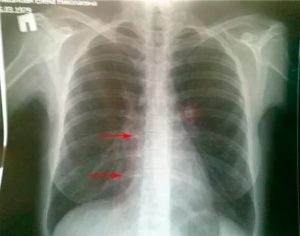

При туберкулезе легкого развиваются следующие патологические процессы:

- легочная недостаточность;

- ателектаз;

- стеноз бронхов;

- эмпиема плевры;

- свищи в легких.